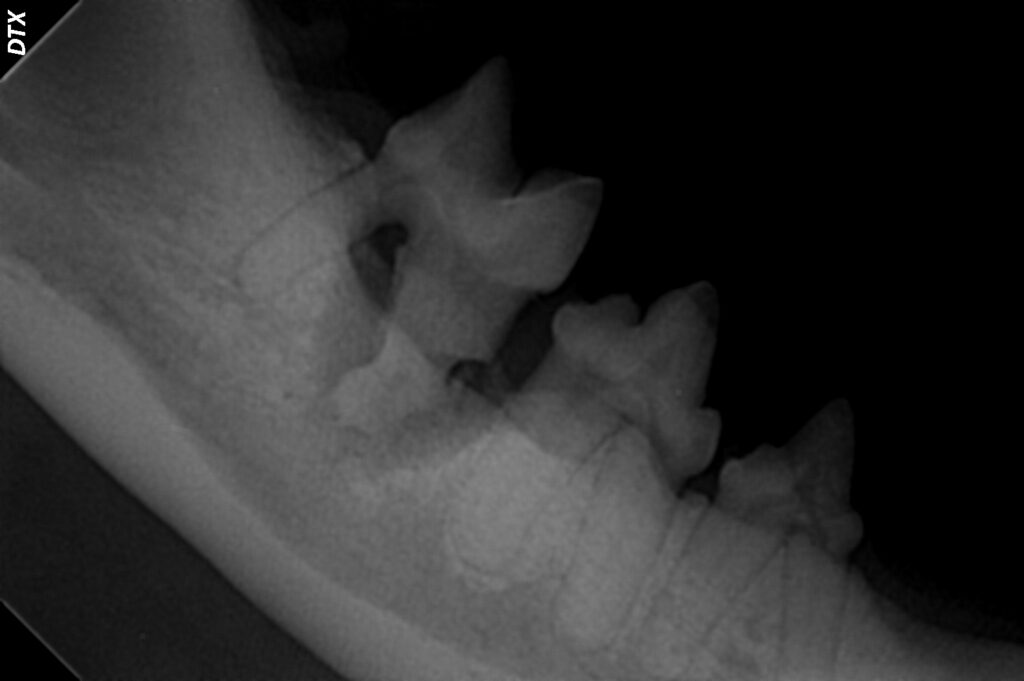

We have digital dental radiography (X-rays) available, providing detailed images of the tooth roots and surrounding structures that are critical for identifying hidden problems below the gumline.